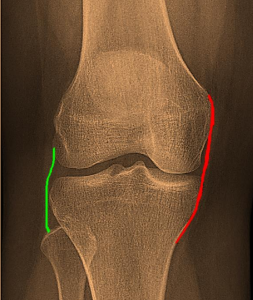

These ligaments work together to stabilize the knee. Other soft tissues such as the capsule and menisci also help provide stability. In general, the cruciate ligament prevents the tibia from displacing anteriorly or posteriorly relative to the femur and provides side-to-side stability to the leg. The deforming force created by blowing on the outside of the knee. The MCL also works with the ACL to prevent axial rotation of the knee. The MCL originates at the medial epicondyle of the femur, inserts into the medial aspect of the tibia, and continues downward for several centimeters. The deep fibers of the MCL extend to the medial meniscus and are separated from the superficial fibers by a bursa. The posterior fibers of the deep MCL blend with the posteromedial capsule and the posterior oblique ligament. MCL can withstand up to 4000N of force without tearing. Deformity of the midline; Varus refers to deformity from the center to the middle. This term is often used in connection with the knee. leg". As seen in Figure 3.)

Figure 3: A normal alignment of the knee to the left; valgus in the middle; and varus to the right.